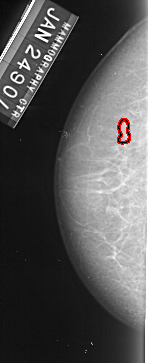

A_1003_1.LEFT_MLO

LEFT_MLO LINES 4996 PIXELS_PER_LINE 1936 BITS_PER_PIXEL 16 RESOLUTION 42 OVERLAY

FILE: A_1003_1.LEFT_MLO.OVERLAY

TOTAL_ABNORMALITIES 1

ABNORMALITY 1

LESION_TYPE CALCIFICATION TYPE PLEOMORPHIC DISTRIBUTION CLUSTERED

ASSESSMENT 4

SUBTLETY 3

PATHOLOGY MALIGNANT

TOTAL_OUTLINES 1

BOUNDARY